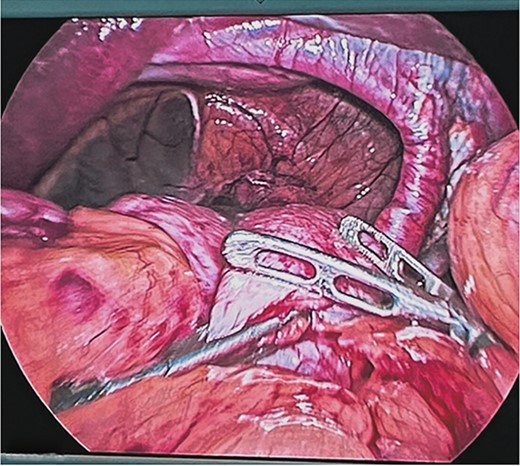

At the end of the dissection of both diaphragmatic crura, their plasty was performed by placing six single 2-0 polypropylene suture stitches with an atraumatic needle with extracorporeal knots at both ends of the hiatus, reducing its size to 5 cm. Subsequently, a composite mesh with a resorbable coating was fixed with automatic laparoscopic staples, reducing the hiatus by up to 3 cm (Fig. 5). Finally, a Toupet fundoplication was performed as an anti-reflux mechanism (Fig. 6).

Placement of composite mesh with resorbable coating and fixing it with automatic titanium spiral sutures reducing the esophageal hiatus up to 3 cm.